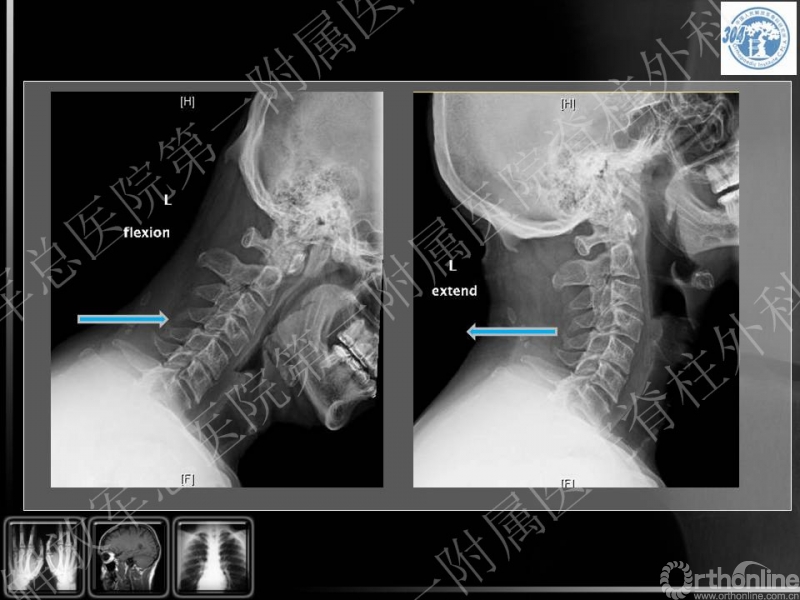

72岁 男性,既往体健,无严重基础疾病,6年前腰椎手术史

右侧前臂外侧及右拇指麻木疼痛,影响睡眠,超过3月不缓解,双手协调控制差

四肢关键肌肌力基本正常,肌张力增高,步态改变

腱反射亢进,双侧Hoffman征(+)

本病例的特点为患者既往有颈椎病的基础,近期出现右上肢疼痛、麻木症状,老年,专家讨论要点主要集中在患者手术前后路选择,节段选择及手术时机等。

李放教授:

患者缺乏X光片颈椎管椎管比值的测量,但基本可见患者有明确的发育性颈椎管狭窄,又有颈椎退变增生的病理基础,核磁见多节段的颈脊髓压迫,近期出现右上肢疼痛麻木症状,体格检查脊髓和单一神经根损害表现,为混合型颈椎病(脊髓型/神经根型)。可考虑行颈椎管扩大成形术,包括单开门/双开门等方式,结合单一神经管切开减压,可达到全面的治疗效果。